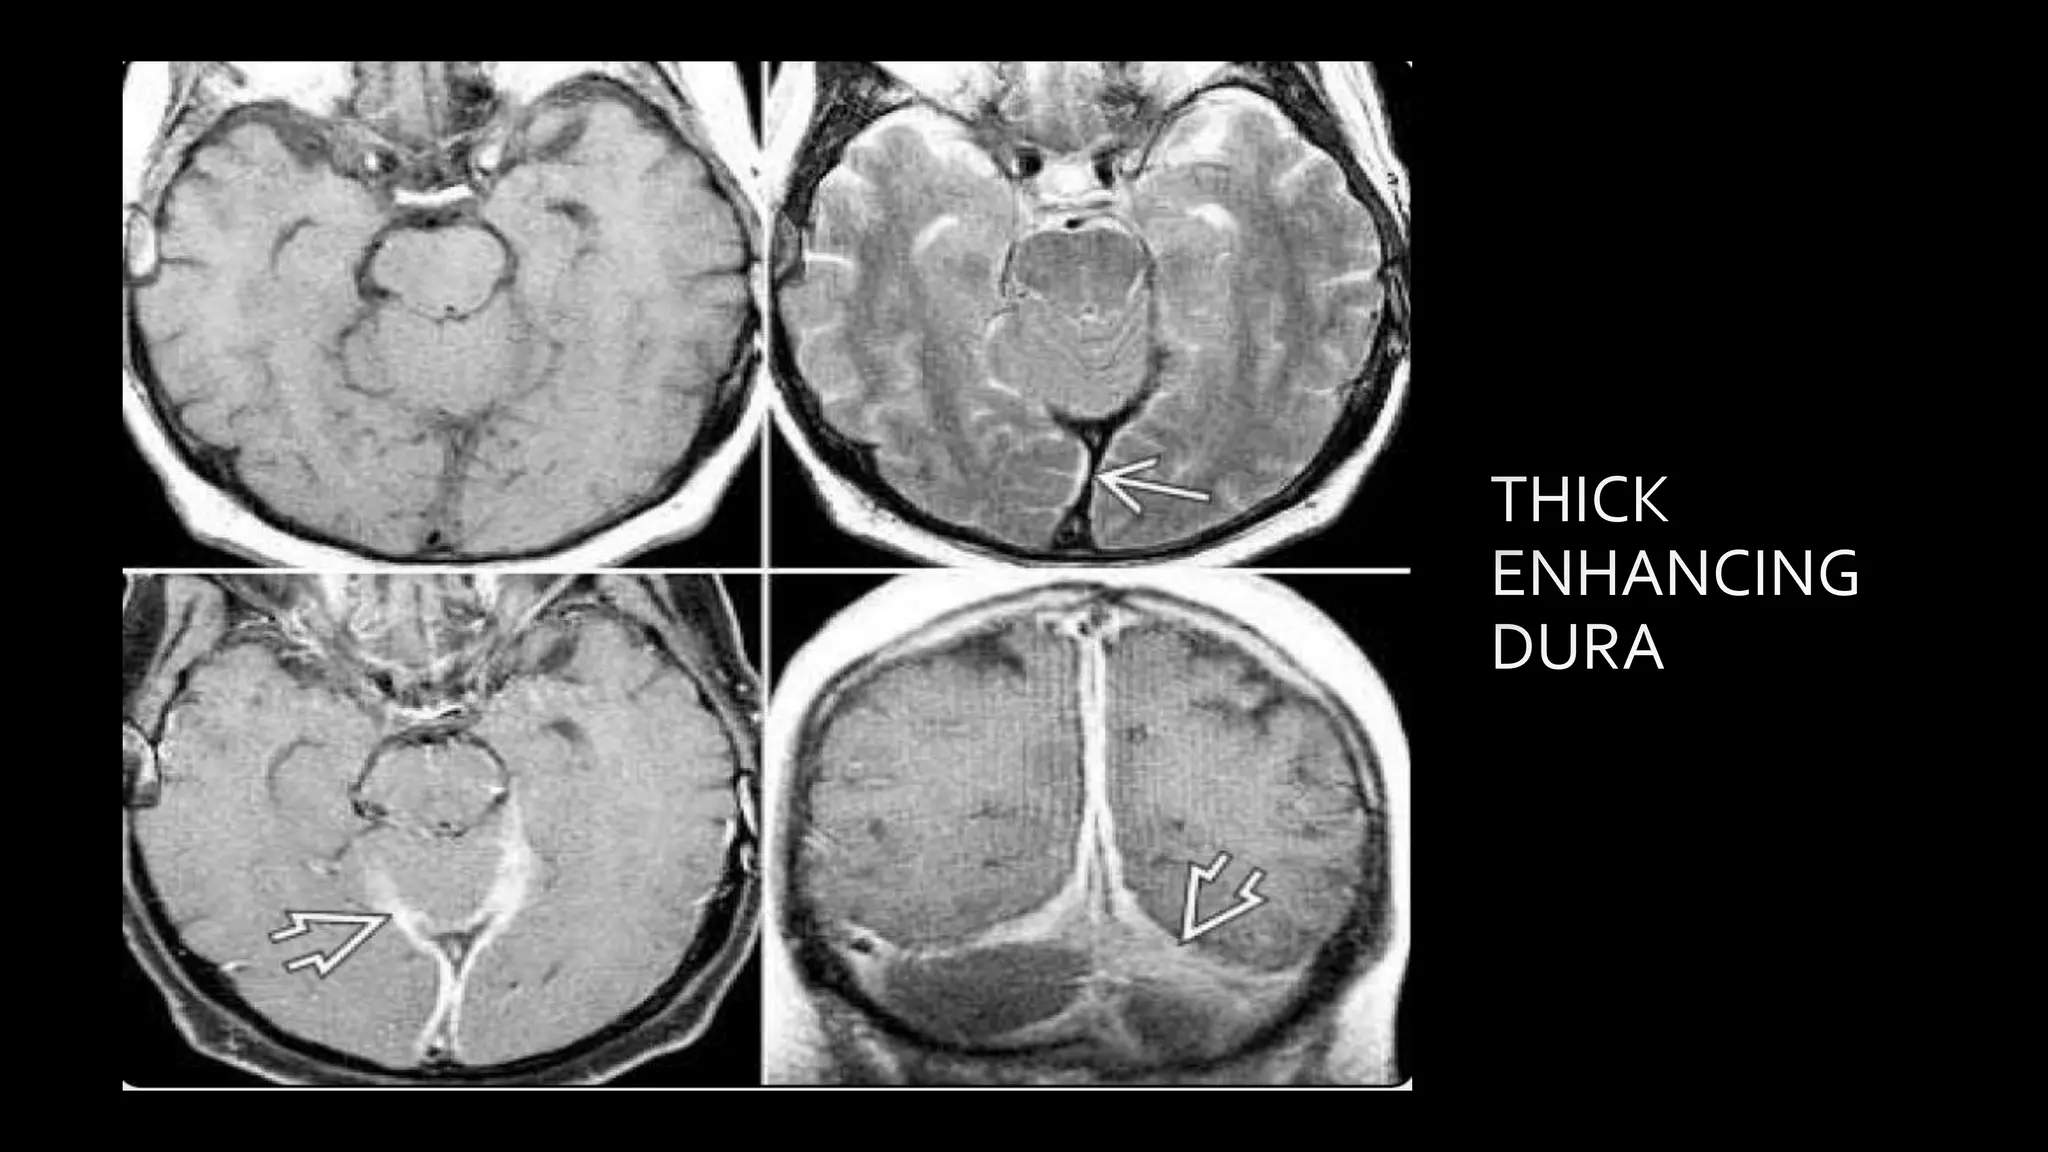

Chronic DST

"squiggly" parenchymal enhancement

• #138 Subacute thrombus appears hyper on all sequences….. Clot signal in chronic dst is variable and depends on organization of clot….. LONG STANDING DST MAY DEVELOP SIGNIFICANT COLLATERAL FORMATION THROUGHT MEDULLARY VEINS WHICH IS SEEN AS SQIGGLY PARENCHYMAL

• #139 T2 * SWI shows innumerable prominent tortuous corkscrew squiggly medullary veins throughout both cerebral hemisphers . Venous DSA shows that distal SSS is occluded while proximal and mid seg are patent . Numourous enlarged medullary veins appears to hang in space . This is chronic SSS thrombosis with medullary collateral draingae

• #140 c/o Long standing chronic sss showing thick dural enhancement alonmg tentorium.